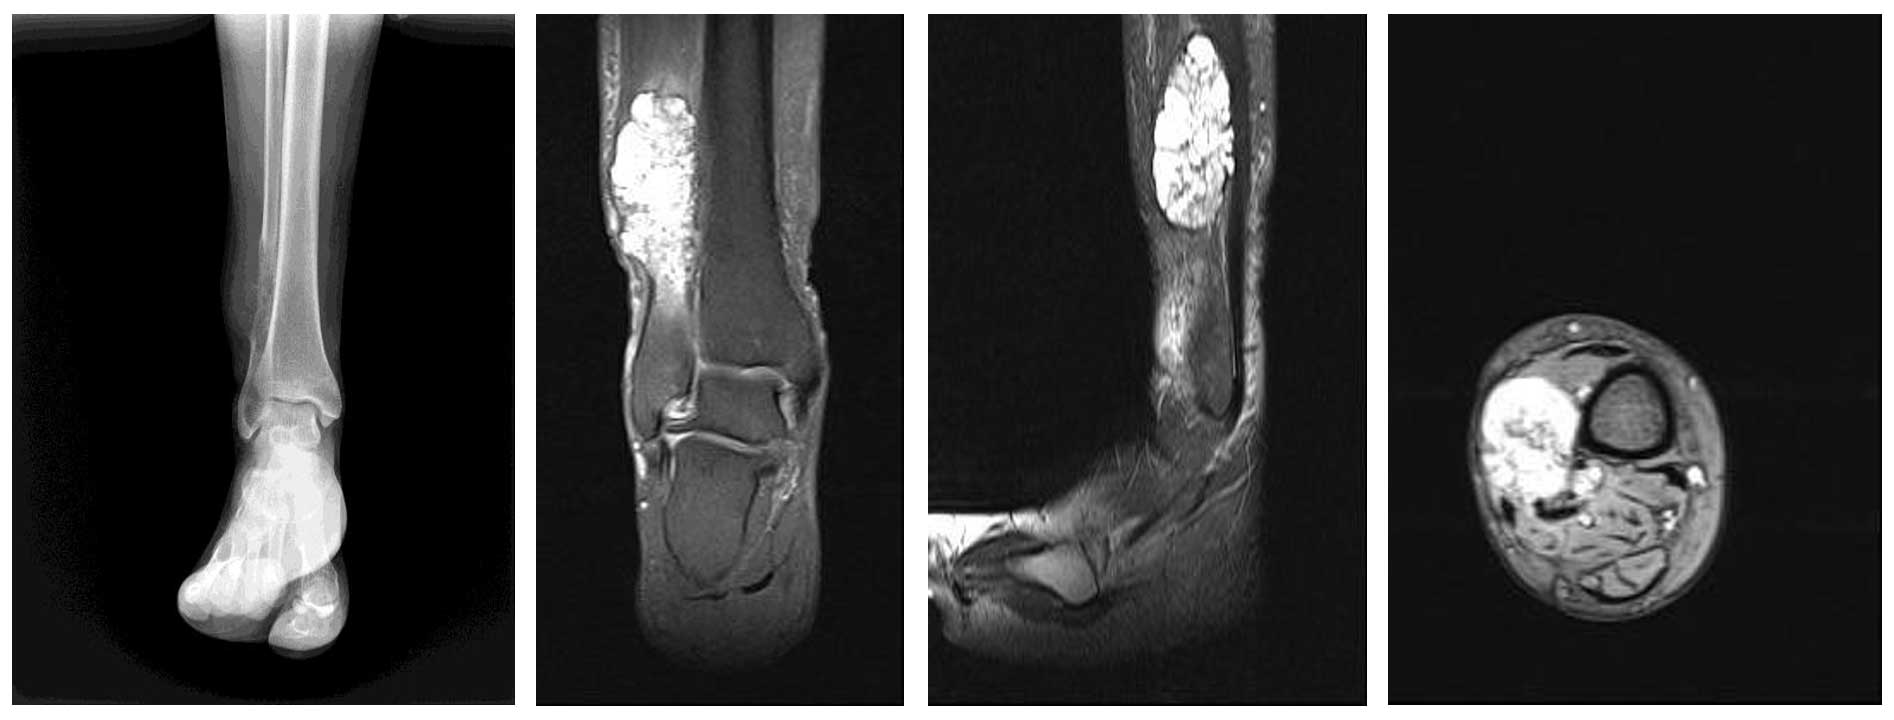

Ameliyat Öncesi: Röntgende distal femurda litik lezyon, MR’da büyükçe yumuşak doku komponenti görülmekte